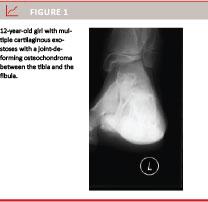

MCE is caused by a mutation in the family of tumour suppressor genes called exostotin (EXT), especially mutations in chromosome 8 (EXT1), 11 (EXT2) and 19 (EXT3), and is dominantly inherited (Figure 1 and Figure 2) [8]. The EXT1 and EXT2 mutations change the function of the glycoprotein glycosyltranferase. This protein is responsible for correct cellular growth, differentiation, movement and adhesion of the cell [6]. The pathology of EXT3 mutations is unknown and accounts for a small amount of the patients [8].

The MCE patients’ clinical symptoms are localised pain, cosmetic disturbances, abnormal osseous growth and deformities of joints [1-16]. The latter can result in low stature, discrepancy of leg length, valgus deformities in the knee and ankle, asymmetric pelvine and pectoral regions and bending of the radius bone resulting in subluxation of carpus [8]. Treatment is surgical resection since this prevents or reduces the progression of deformities and functional impairment caused by an OC (Figure 3). Otherwise, treatment is not recommended in asymptomatic cases [14].